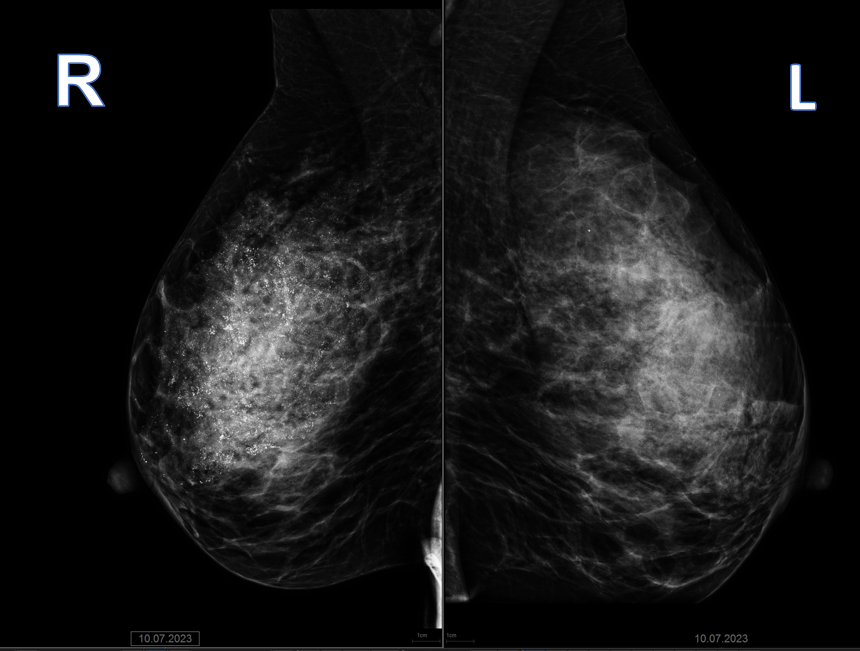

На приеме пациентке была выполнена маммография: в правой молочной железе в верхнем наружном квадранте определяется зона микрокальцинатов типа фрагментированных слепков размером 15х7,1х7,8 см с признаками распространения на связки Купера, кожу сосково-ареолярной зоны -  BIRADS 5 (рис. 1, 2).

Рис. 1 Маммограммы правой и левой молочной железы в косой проекции R MLO и L MLO, в правой молочной железе – множественные тени кальцинатов по типу слепков протоков.

Рис. 2 Маммограммы правой и левой молочной железы в прямой проекции R СС и L СС, в правой молочной железе – множественные тени кальцинатов по типу слепков протоков.